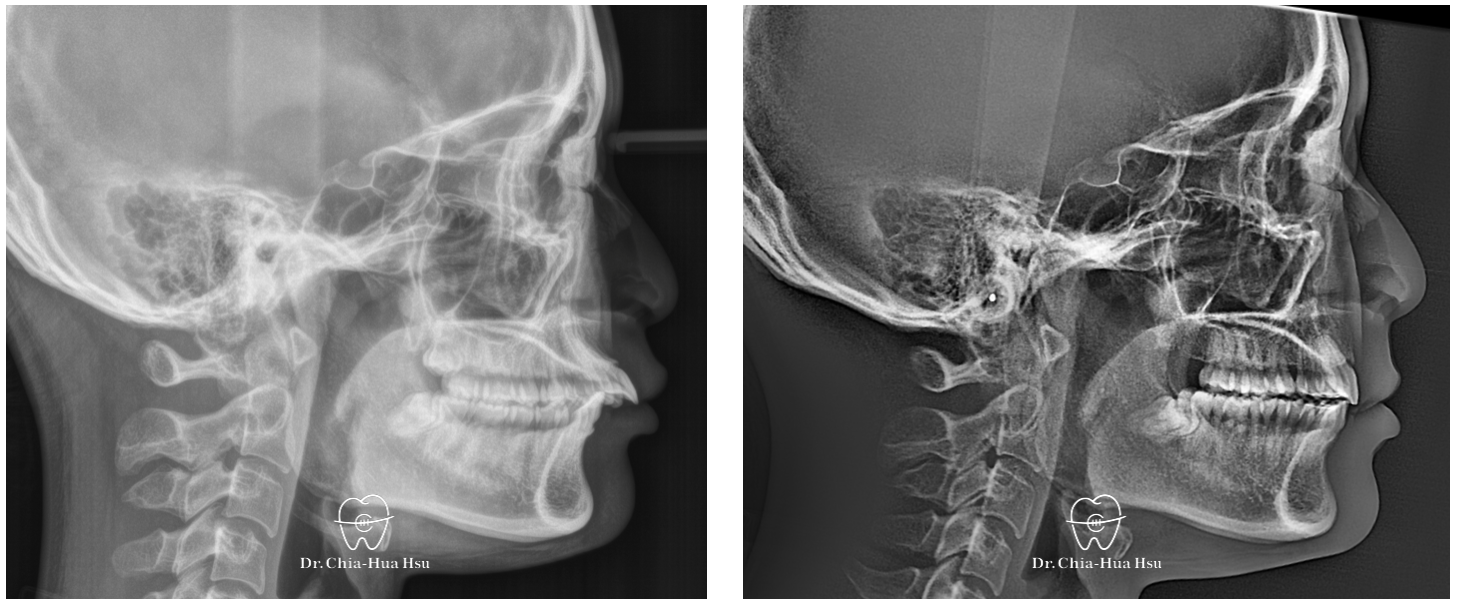

• 問題分析:患者是牙齒二類咬合(Skeletal Class II)、方臉型、暴牙以及齒列不整齊。

• 治療方式:使用傳統金屬矯正器,考量到患者臉型不適合退太多,因此只拔除上顆兩顆小臼齒以及兩支暫時性迷你骨釘來完成治療。

• 治療時間:2 年 7 個月。

• 治療結果:齒列排齊,嘴凸改善,外觀變得更和諧,笑容也更有自信。